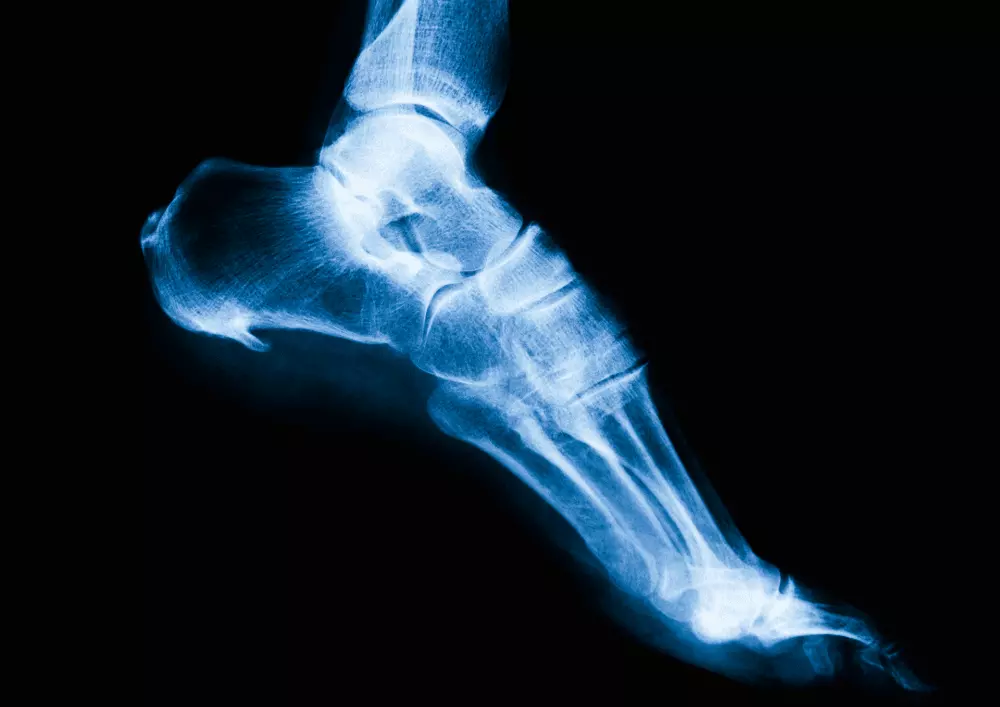

- ćwiczenia na płaskostopie

W tej samej rubryce publikujemy również przykładowe ćwiczenia na płaskostopie. Choć każde dziecko rodzi się z płaskostopiem fizjologicznym, z czasem ono zanika, a mięśnie stóp wzmacniają się. Mimo to, jest to częsta wada kończyn dolnych u dzieci wywołana przez źle dobrane obuwie lub zbyt szybką naukę chodzenia. Konieczne są wówczas ćwiczenia na płaskostopie oraz odpowiednio dobrane wkładki ortopedyczne.